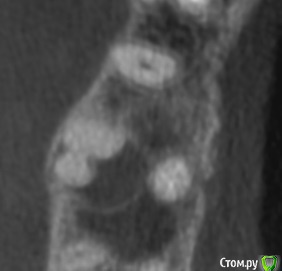

vse32 Опубликовано 6 ноября, 2019 Поделиться Опубликовано 6 ноября, 2019 Я стоматолог терапевт, поэтому вопрос почти как от обывателя.16 зуб, женщина около 35 лет (не видела ее, коллега мужа по работе). В сторонней клинике сделали ОПТГ и КТ и рекомендовали удаление с одномоментной имплантацией. Со слов женщины предложен корейский имплантат за х рублей + подсадка за х рублей. Или американский имплантат за 2х рублей без подсадок.Вопрос - нормально ли это делать одномоментно при наличии кистогранулемы (вне обострения).Лечить эндодонтически могу, но сомневаюсь в гарантийности работы. Ссылка на комментарий

колесников Опубликовано 7 ноября, 2019 Поделиться Опубликовано 7 ноября, 2019 (изменено) всё возможно в этой жизни. Интересно посмотреть такой кейс. Но это смущает а что Вас смущает? Ситуация очень благоприятная,киста сама сделала синуслифтинг,если сделаем паузу-потеряем этот объём Изменено 7 ноября, 2019 пользователем колесников 4 Ссылка на комментарий

Irouil Опубликовано 11 ноября, 2019 Поделиться Опубликовано 11 ноября, 2019 (изменено) красивая идея и фото, но как фиксирован имплант? просто лежит в графте?Бикортикально (вернее - в кортикалке дна пазухи) и в перегородке, там где она осталась. Если широкий винт - в стенках лунки. В таких рейсах и 10 Н*см достаточно Изменено 11 ноября, 2019 пользователем Irouil 1 Ссылка на комментарий

колесников Опубликовано 11 ноября, 2019 Поделиться Опубликовано 11 ноября, 2019 (изменено) Просто лежать в графте на в/ч он не может,силу тяжести никто не отменял. Имплант обязательно должен контактировать с нативной костью и иметь хоть минимальную ,но стабильность. Стабильность,как ответили выше ,можно получить зацепившись апексом за свод, где то за перегородку,и фдм иногда помогает. Были случаи стабильности только от супраструктуры и имплант интегрировался.Это не просто идея и красивое фото,это вполне себе рабочая модель Изменено 11 ноября, 2019 пользователем колесников 4 Ссылка на комментарий